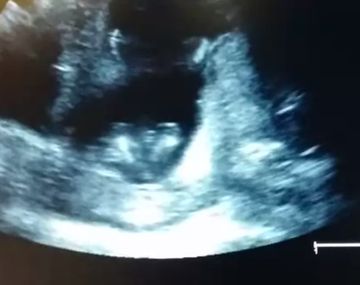

¿Un feto de 14 semanas aplaude? Se trata de un video que registró el momento durante el estudio médico. "Fue increíble. El bebé aplaudió tres veces", aseguró Jen Cardenal, la futura mamá, al referirse a las imágenes capturadas. YouTube